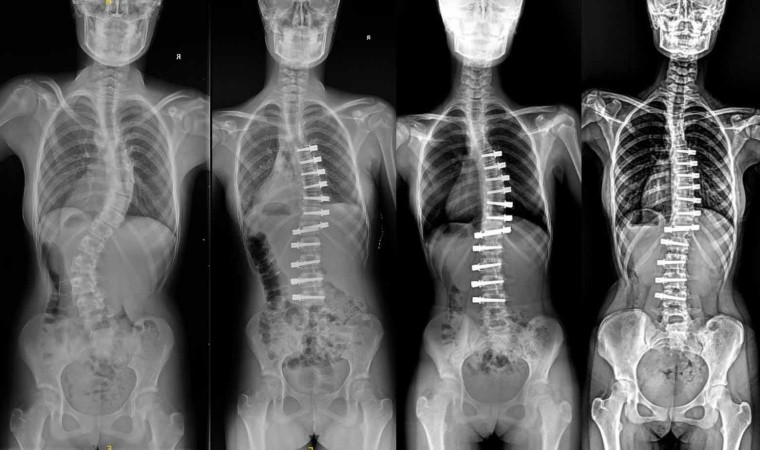

Ortopedi ve Tramvatoloji Uzmanı Doç. Dr. Tuna Pehlivanoğlu, çocuk hastalar için umut olan ipli skolyoz ameliyatını anlattı. Pehlivanoğlu, "Bu teknik devrim niteliğinde, çocukların büyümesine ve gelişmesine izin veren bir yöntem. Burada yaptığımız iş klasik ameliyattaki gibi sırttan büyük bir kesik yapmak değil. Göğüs boşluğuna kenardan ufak kesik yaparak vidaları kamera yardımıyla koyuyoruz. Araya da bir ip gerdiriyoruz. Gerdirmeyle eğriliği yani skolyozu düzeltiyoruz. Sonrasında çocuk büyüyerek kendi kendisini de düzeltiyor. Bu ameliyat eskiden tek bir taraftan yapılabiliyordu. Vidalar tek bir taraftan koyulabiliyordu. Biz bunu iki taraftan da yapılabilir hale getirdik" dedi.

Ortopedi ve Tramvatoloji Uzmanı Doç. Dr. Tuna Pehlivanoğlu, skolyoz hastası çocukların tedavisi hakkında konuştu. Genelde çocuklarda skolyoz hastalığının görüldüğünü belirten Pehlivanoğlu, 40 derecenin üzerindeki eğriliklere ameliyatla tedavi önerildiğini söyledi. Klasik skolyoz ameliyatında omurgaya arkadan yerleştirilen vidalar nedeniyle çocukların omurgalarında hareket engelinin meydana geldiğini ifade eden Pehlivanoğlu, tedavinin sonucunda çocukların büyüme ve gelişmelerinin durduğunu kaydetti. Ancak geliştirilen ipli ameliyat yöntemiyle skolyoz hastası çocukların büyüyüp gelişebileceğini belirten Dr. Pehlivanoğlu, ameliyatı uyguladıkları profesyonel sporcuların ve dansçıların da olduğunu aktardı. Ameliyat yöntemi hakkında bilgi veren Doç. Dr. Tuna Pehlivanoğlu, göğüs boşluğunun kenarından küçük kesik yaparak vidaların kamera yardımıyla koyulduğunu ardından da araya bir ip gerilerek skolyozu düzelttiklerini anlattı. Bu yöntemi göğüs boşluğunun iki tarafından da vida yerleştirerek uygulanabilir hale getirdiklerini söyleyen Pehlivanoğlu, eğriliği fazla olan çocuklara vidaların bir kısmının sağdan bir kısmının ise soldan yerleştirildiğini belirtti. Öte yandan tedavinin büyüme potansiyeli olan, büyümesi devam eden, eğriliği esnek olan ve genelde 60-65 dereceyi geçmeyen hastalara uygulandığını da aktardı.

Ameliyat yöntemini uygulamada dünyadaki öncülerden bir tanesi olduklarını ifade eden Pehlivanoğlu, "Burada yaptığımız iş klasik ameliyattaki gibi sırttan büyük bir kesik yapmak değil. Göğüs boşluğuna kenardan ufak kesik yaparak vidaları kamera yardımıyla koyuyoruz. Araya da bir ip gerdiriyoruz. Gerdirmeyle eğriliği yani skolyozu düzeltiyoruz. Sonrasında çocuk büyüyerek kendi kendisini de düzeltiyor. Bu ameliyat eskiden tek bir taraftan yapılabiliyordu. Vidalar tek bir taraftan koyulabiliyordu. Biz bunu iki taraftan da yapılabilir hale getirdik. Yani eğriliği daha fazla olan çocuklarda vidaların bir kısmını sağ taraftan, bir kısmını da sol taraftan koyuyoruz. Bu şekilde düzeltiyoruz. Eskiden ipli skolyozla bunu yapmak mümkün değildi. Biz dünyada ilk olarak bunu uygulayıp literatürde de yayınlayarak mümkün olduğunu gösterdik. Artık o çocuklarda ipli skolyozla tedavi olabiliyorlar. İpli skolyoz herkese uygulanmaz. İpli skolyozu uygulayabileceğimiz hastalar, büyüme potansiyeli olan, büyümesi devam eden, eğriliği esnek olan ve genelde 60-65 dereceyi geçmeyen hastalara uyguluyoruz" şeklinde konuştu.